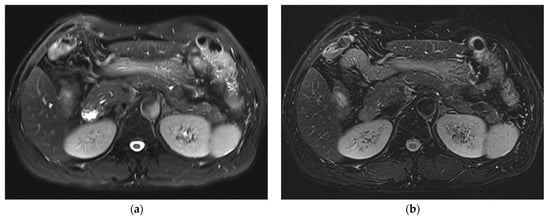

Improved Single Breath-Hold SSFSE Sequence for Liver MRI Based on Compressed Sensing: Evaluation of Image Quality Compared with Conventional T2-Weighted Sequences

3. Results

3.1. Subjective Image Quality

3.2. Lesion Assessment